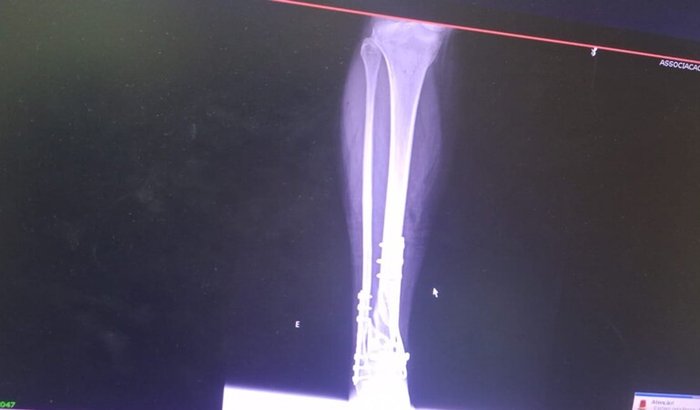

Sou Fabiana quebrei a perna em uma queda de esacada ,operei pela emergencia

Teria que fazer essa nova cirrurgia pois o osso.ficou mal posicao

Com isso posso ter a perna amputada pois o osso não ta colando dependo mto dessa ajuda